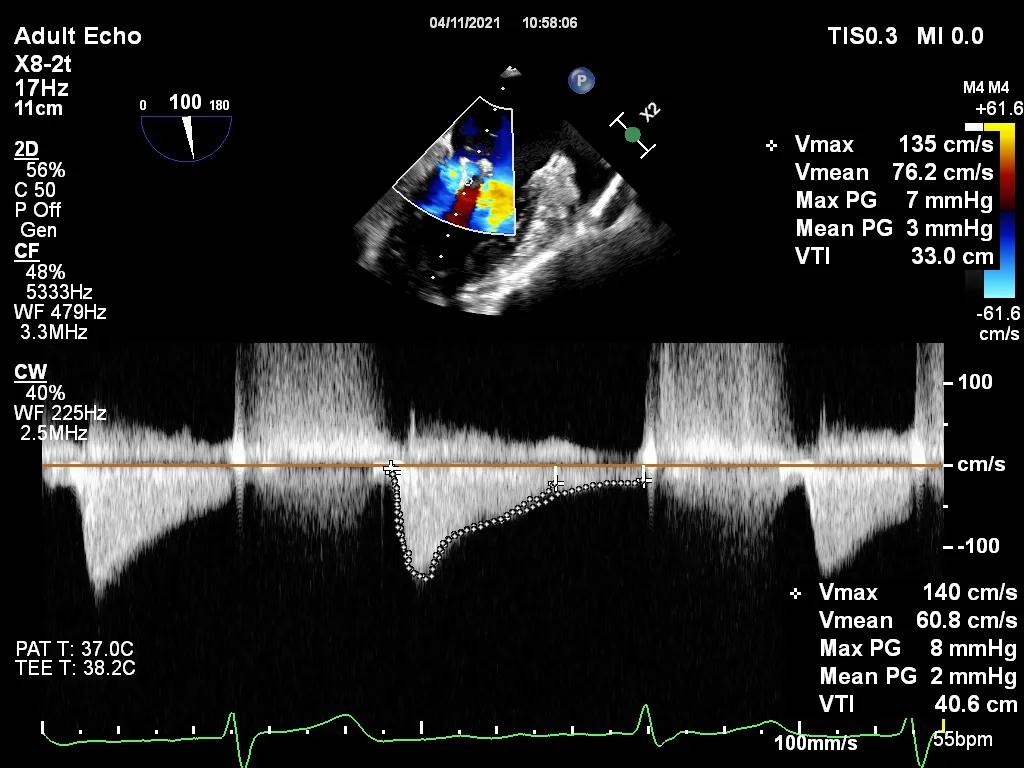

图1 两枚夹合器植入后,未致二尖瓣口狭窄,二尖瓣平均跨瓣压差为3mmHg

4月11日上午患者在全麻下接受MitraClip经皮二尖瓣夹合术。术中穿刺右股静脉,经食道超声心动图(TEE)再次评估瓣膜病变(视频1),并引导顺利穿刺房间隔(视频2)。随后送入二尖瓣夹合系统,在TEE引导下于二尖瓣P2区植入MitraClip XTR夹合器一枚(视频3),二尖瓣关闭不全减轻,但夹合器内侧仍存在反流(视频4)。团队决定为患者植入第二枚夹合器(MitraClip NTR),手术过程顺利(视频5)。TEE三维显示在植入第二枚NTR夹合器后,二尖瓣呈双孔启闭,两枚夹合器位置、结构正常(视频6)。配备心腔镜功能的TEE三维TrueVue彩色多普勒显示二尖瓣反流将至少量(视频7),且未致二尖瓣口狭窄(图1),夹合效果满意。手术通过视频连线得到香港亚洲心脏病中心主任林逸贤教授的技术支持。